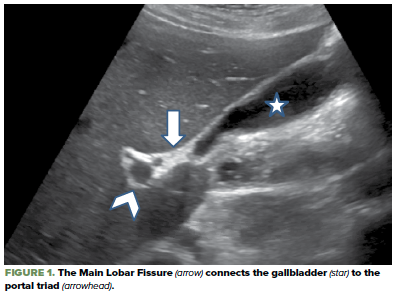

Where In The World Is The Cbd Ultrasound Tips For Finding The Common Bile Duct Emra